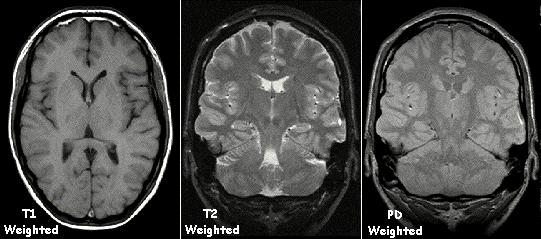

수소 원자핵이 원래 상태로 돌아오는 시간(완화 시간)은 주변 조직에 따라 다르며, 이 차이를 이용하여 T1 강조 영상, T2 강조 영상 등 다양한 영상을 얻을 수 있다.[167] 수소 원자핵의 스핀이 주변의 수소 원자핵의 스핀과의 상호작용에 의해 완화되는 것을 스핀-스핀 완화라고 하고, 이에 의한 시간 상수를 T2라고 한다.[167] 이와 달리, 스핀이 주변 조직의 격자 구조와의 상호작용에 의해 완화되는 것을 스핀-격자 완화라고 하고, 이 시간 상수를 T1이라고 한다.[167]

T1 강조 영상을 생성하기 위해, 반복 시간(TR)을 변경하여 MR 신호를 측정하기 전에 자화가 회복되도록 한다. 이 영상 가중치는 대뇌 피질 평가, 지방 조직 식별, 국소 간 병변 특징 분석, 일반적인 형태 정보 획득, 그리고 조영제 투여 후 영상 촬영에 유용하다.

T2 강조 영상을 생성하기 위해, 에코 시간(TE)을 변경하여 MR 신호를 측정하기 전에 자화가 감쇠되도록 한다. 이 영상 가중치는 부종과 염증 검출, 백색질 병변 확인, 그리고 전립선과 자궁의 구역 해부학 평가에 유용하다.

자기공명영상의 표준 표시는 흑백 영상에서 체액 특성을 나타내는 것이며, 서로 다른 조직은 다음과 같이 나타난다.신호 T1 강조 T2 강조 높음 style="vertical-align:top;"| style="vertical-align:top;"| 중간 style="vertical-align:top;"| style="vertical-align:top;"| 낮음 style="vertical-align:top;"| style="vertical-align:top;"|